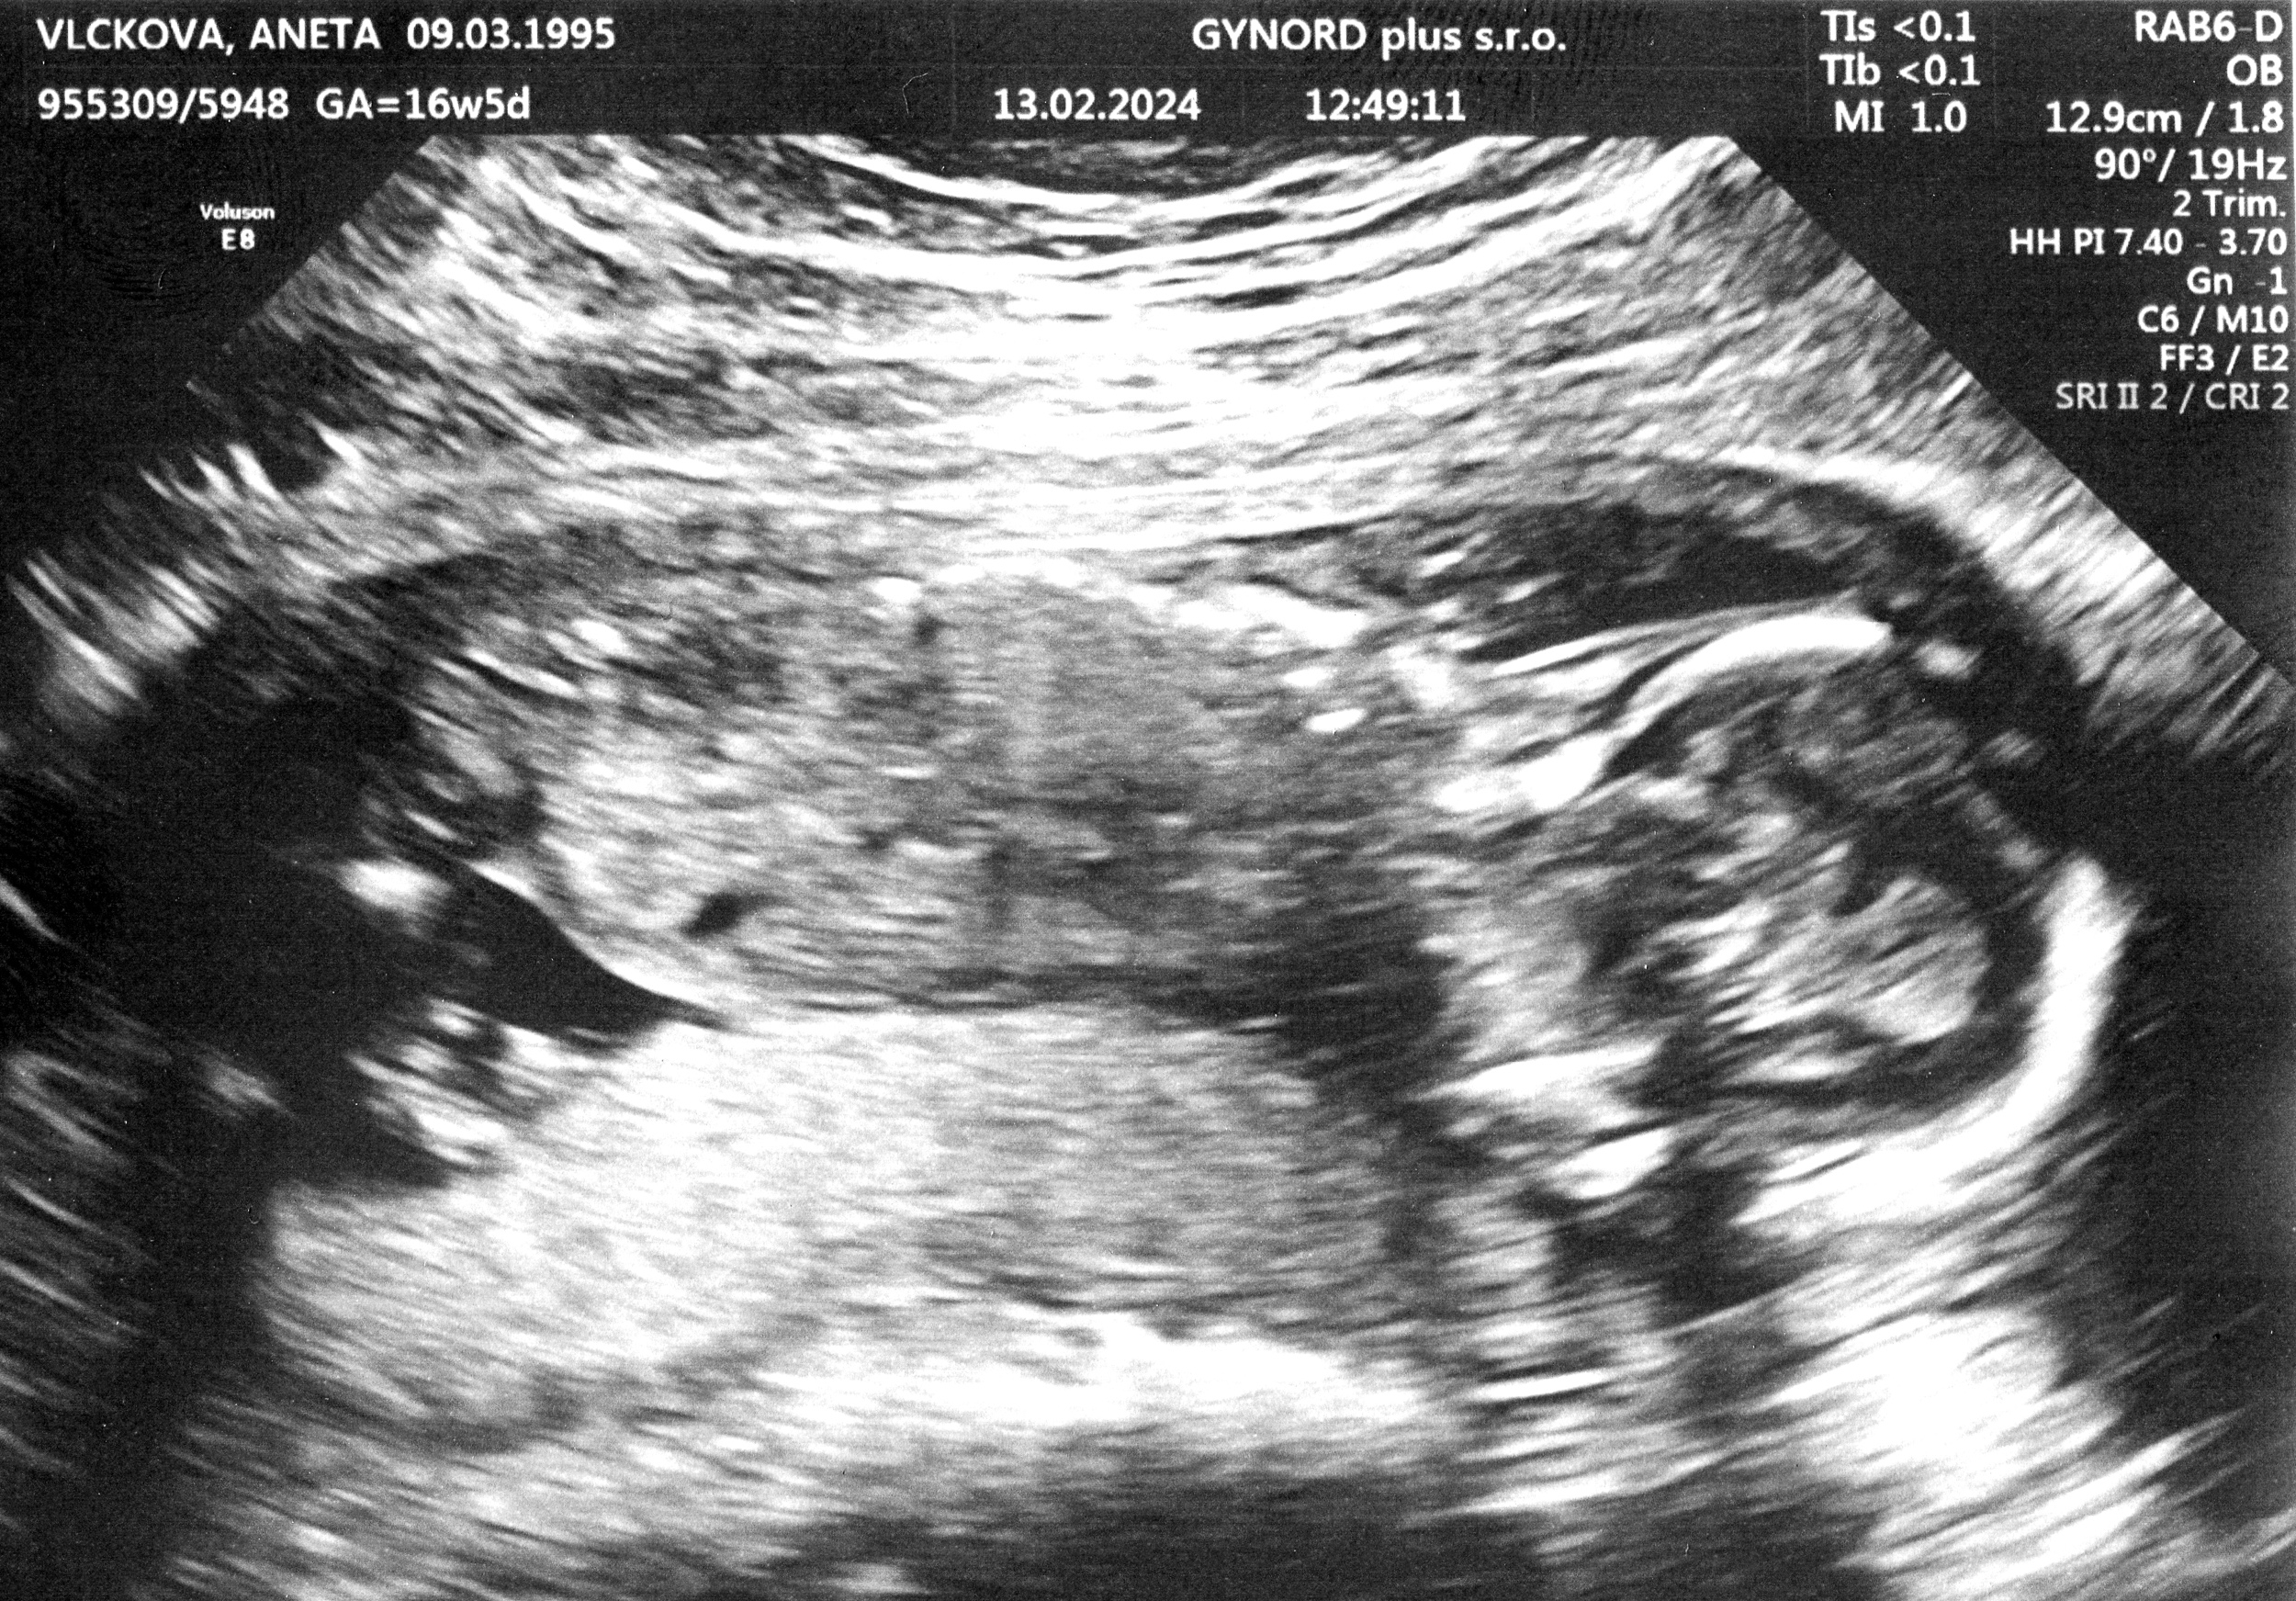

Tomášek - ještě v bříšku